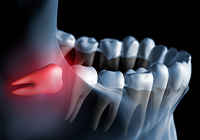

親知らずは10代後半~30代にかけて生えてくる永久歯ですが、炎症や痛みを伴う「智歯歯周炎」を引き起こすことがあります。問題がなければそのまま永久歯として使うことができますが、精密検査を行った上でトラブルの可能性がある場合は抜歯を検討します。親知らずが生え始めたなと思ったら、痛みが出る前に歯科医院を受診しましょう。

1.正常に生えているタイプ

他の歯と同じように使用することが可能

2.埋没タイプ

画像診断の上、抜歯を検討

3.傾斜タイプ

歯周炎のリスクが高い

抜歯を検討